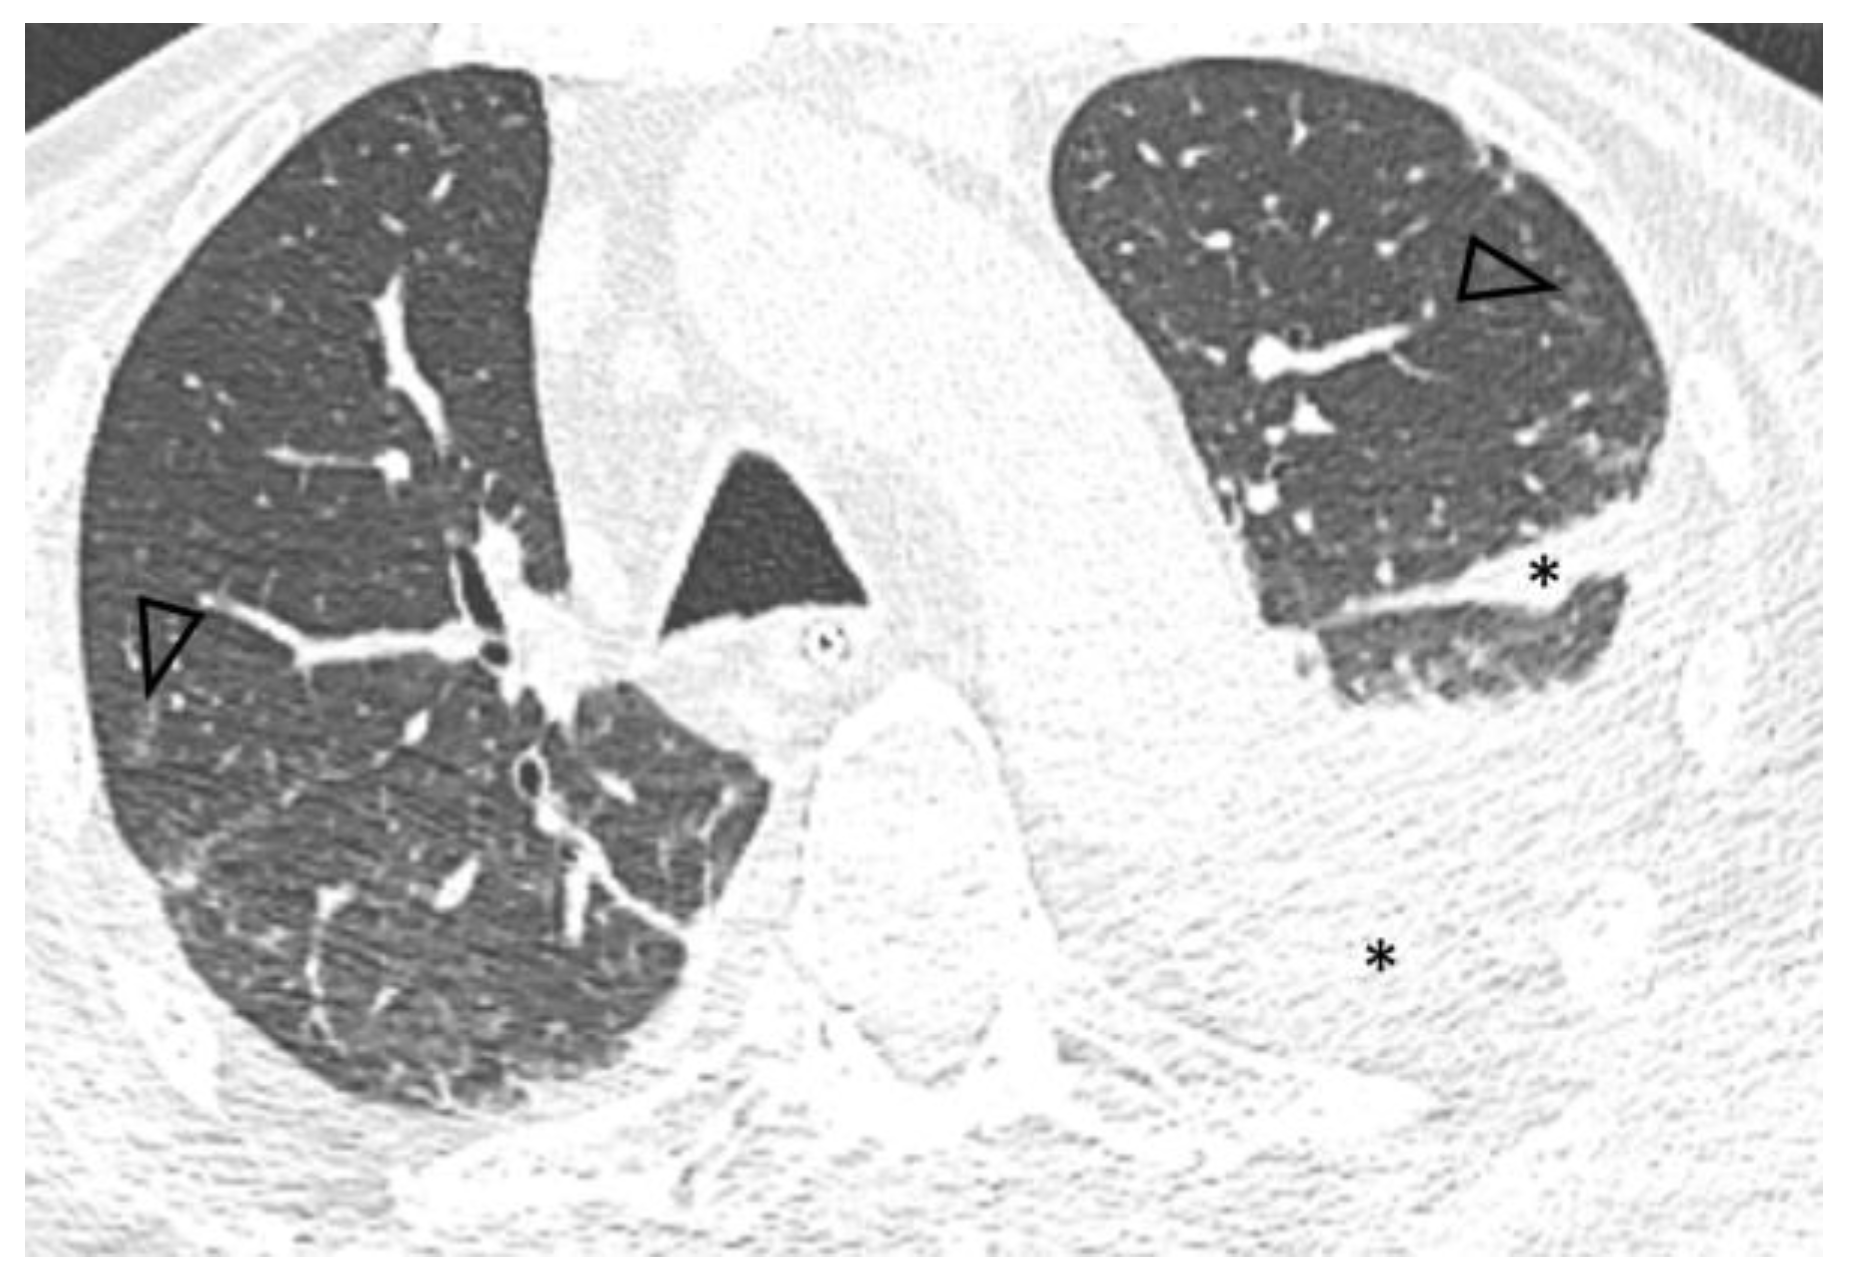

Figure 1.

Axial 0.6 mm slice through the upper lung fields demonstrates asymmetric ground glass (arrowheads) and alveolar (arrows) opacities with a centrilobular distribution. Bilateral pleural effusion (*) is also seen.

A follow-up chest CT performed five months after diagnosis showed significant improvement of pulmonary disease with subtotal resolution of pre-existing ground-glass opacities and increased pleural effusions (Figure 2).

Figure 2.

Axial 0.6 mm slice, level similar to Figure 1, demonstrates subtotal resolution of opacities with residual centrilobular ground glass nodules (arrowheads) and increased left pleural effusion, extending into the major fissure (*).